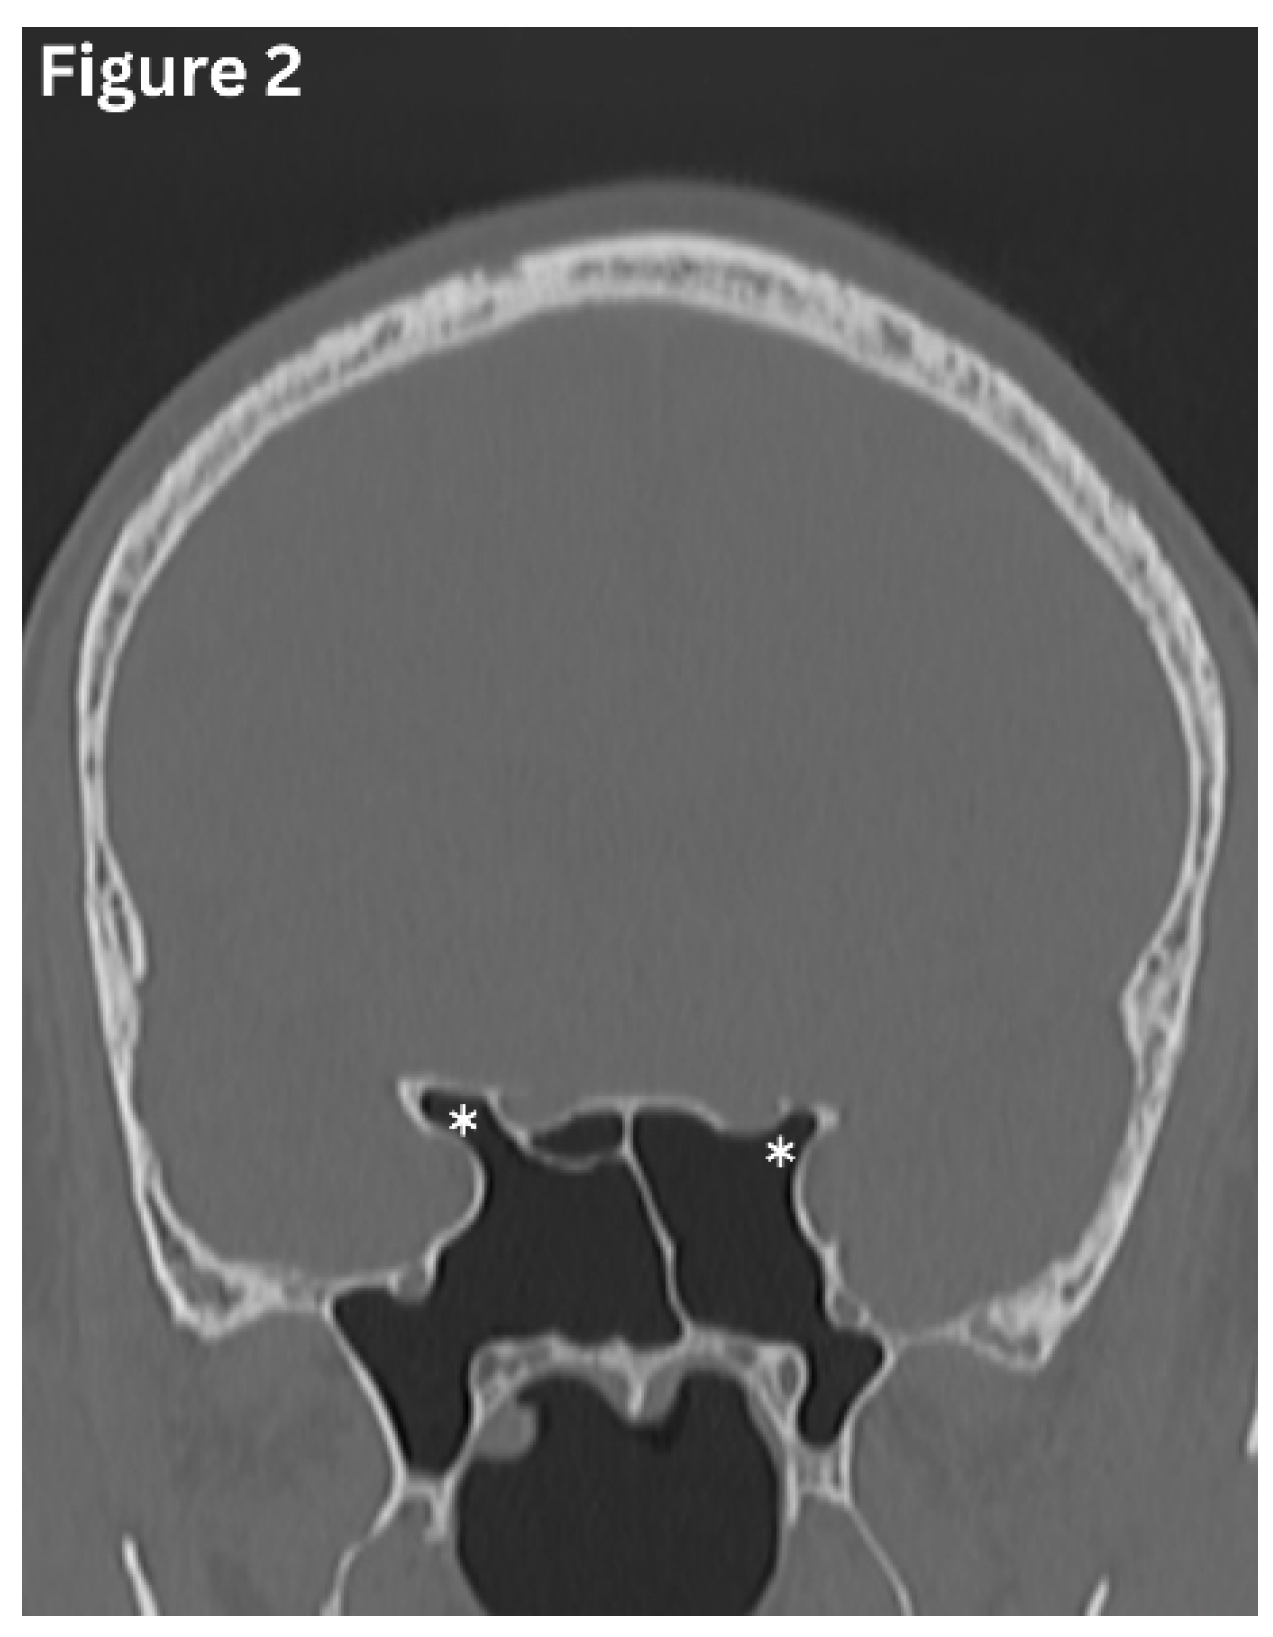

Anatomical variation of the paranasal sinuses is common and has important clinical and surgical implications. Variants of the maxillary sinus include internal septation, the presence of accessory ostia, and varying degrees of sinus hypoplasia. In cases of maxillary sinus hypoplasia, endoscopic intervention carries an increased risk of orbital entry, either through the lamina papyracea or the sinus floor, owing to altered anatomical relationships. (Figure 4) The frontal sinuses frequently exhibit asymmetry in size and extent and are typically separated by a midline bony septum. One or both frontal sinuses may be markedly underdeveloped or absent in certain individuals. The sphenoid sinus demonstrates wide variability of variations, ranging from partial or complete agenesis to extensive pneumatisation, including extension into the clinoid processes and adjacent pterygoid or ethmoid bones. (Figure 2) Variations in sphenoid septation, such as deviation or the presence of multiple septa, further contribute to the complexity of this region and are particularly relevant during surgical planning [9,10] (Figure 3).

Figure 2. Coronal CT image shows pneumatization of the sphenoid sinus extending into the anterior clinoid processes (asterisks).